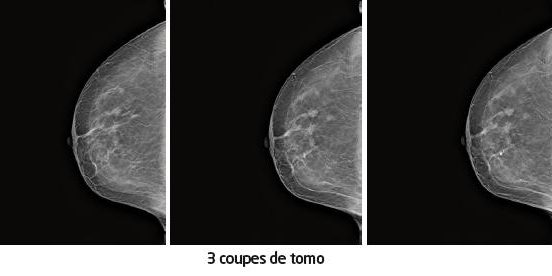

Le CAD (Computer Aided Diagnostic) révèleune imagedans la profondeur du QSE sein droit. Les 72coupes de tomosynthèserévèlent3 images très suspectes : au plus hautdu QSE, en regard de l’image QSED, dans la région sus et rétro aréolaire.

De l’utilité de la tomosynthèse: la mastectomie a confirmé ces lésions (processus trifocal). Ce sein est lipomateux, transparent et seule une de ces lésions a été détectée aux ultrasons 18 MgHZ.